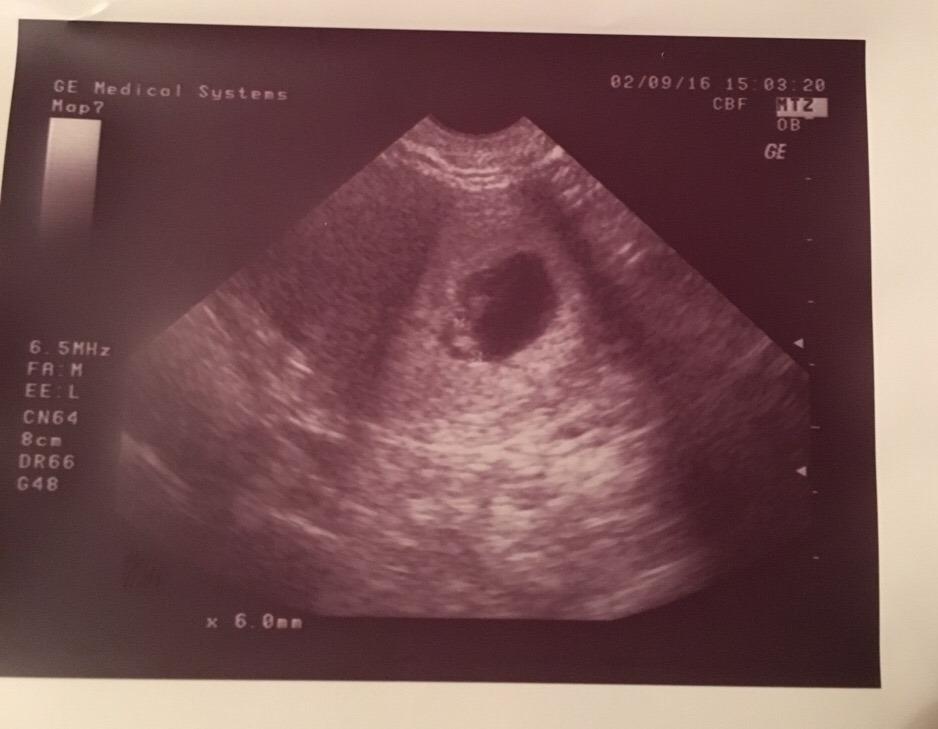

És csatolom az első képet a kis Mikkamakkáról :) Ez 6 hetesen volt pontosan 6 mm volt akkor, már nagyon várom ezt a most pénteki vizsgálatot, hogy újra láthassam